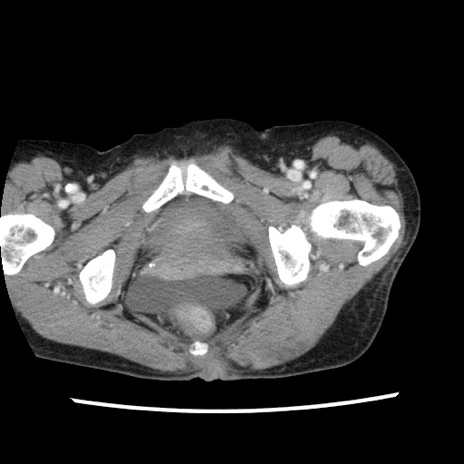

症例1(横断像)

【症例】80歳代女性

【主訴】腹痛

【現病歴】8時間前から腹痛あり来院。

【既往歴】糖尿病、脂質異常症、子宮体癌にて子宮全摘術

【身体所見】意識清明・会話良好だが腹痛で苦悶様、全腹部にわたって反跳痛と圧痛あり

【データ】WBC 13600、CRP 0.14、LDH 224、CK 90